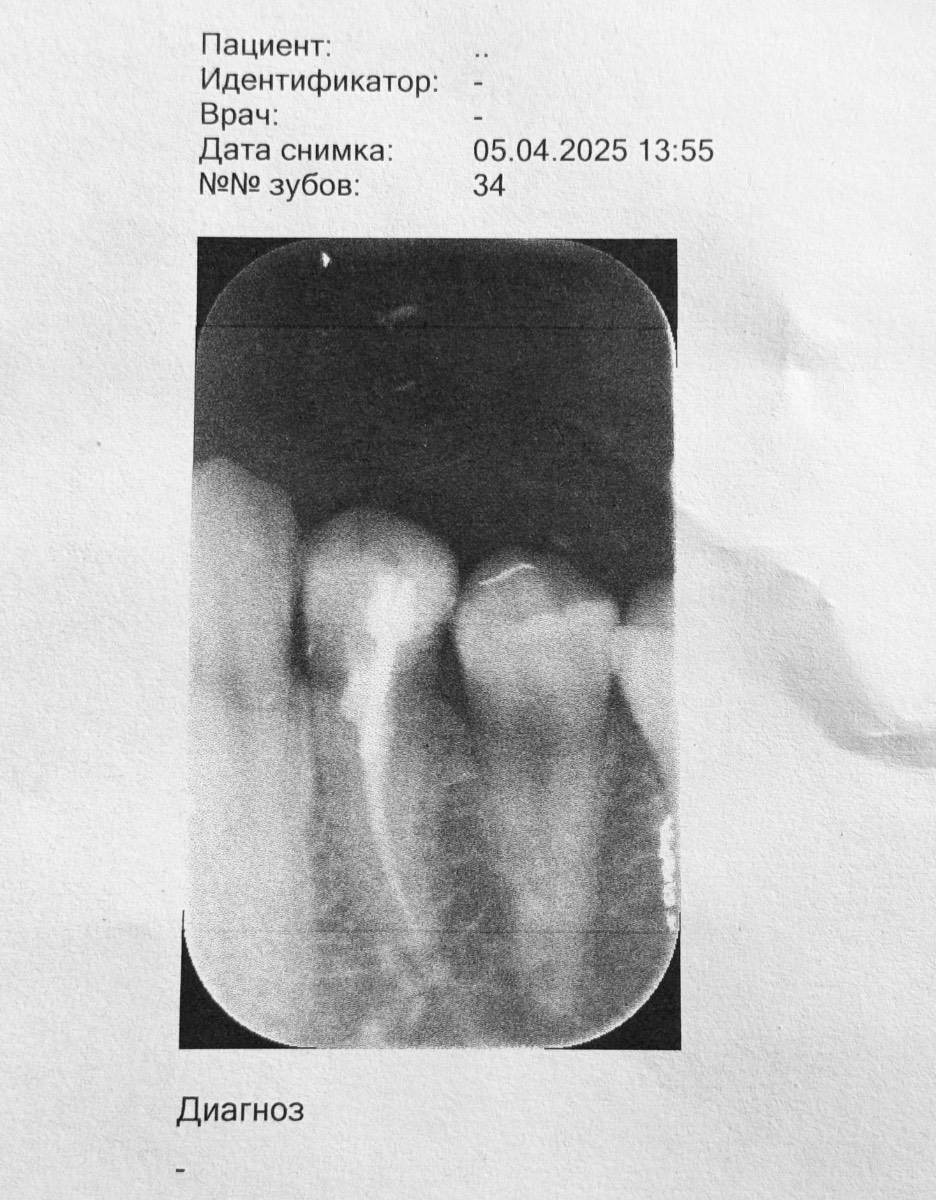

ektbrin Опубликовано 9 апреля, 2025 Автор Поделиться Опубликовано 9 апреля, 2025 (изменено) В 08.04.2025 в 10:27, red_butler сказал: Здравствуйте, покажите рентген Изменено 9 апреля, 2025 пользователем ektbrin Ссылка на комментарий

red_butler Опубликовано 9 апреля, 2025 Поделиться Опубликовано 9 апреля, 2025 качество снимка плохое, как минимум зуб нужно восстановить искусственной коронкой. Сделайте Кт. Ссылка на комментарий